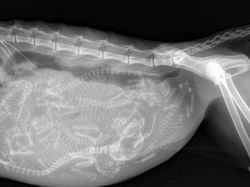

Penampakan dalam tubuh penyu saat hamil. (Foto: Brightside)

Anak-anak kucing yang masih di dalam perut sang induk. (Foto: Brightside)